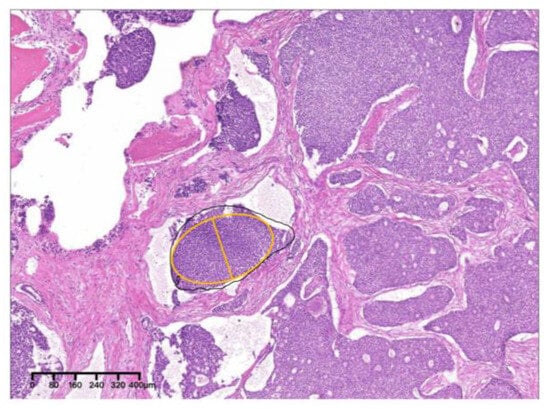

2.1. Case 1